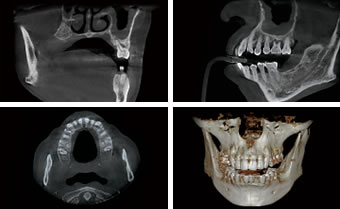

CT:さらに鮮明に、顎骨までカバーできる広範囲の撮影が可能に

CTセンサー(FPD)とパノラマセンサー(CMOS)の自動切替、頭部の自動固定を採用によりモーションアーチファクトの減少。CT撮影時間も最少5.9秒と大幅に被曝量を抑えながらマルチFOV(fieldofview=撮影視野)機能により5×5cmから最大16×10cmの高品質画像を実現した、多岐にわたる歯科治療を支援する機器です。